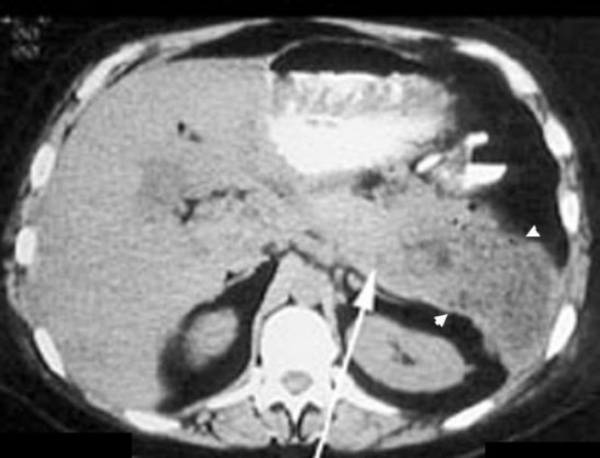

(Правый) При КТ с контрастным усилением на аксиальной томограмме у того же пациента в теле поджелудочной железы определяется псевдокиста. Слоистый детрит на этой томограмме виден плохо, при УЗИ он определяется гораздо лучше.

3. КТ при псевдокисте поджелудочной железы:

• Округлое или овальное гомогенное образование сниженной плотности, плотность почти равна плотности воды («зрелая» псевдокиста)

• Геморрагическая, инфицированная псевдокиста: многокамерное, гетерогенное, неоднородной плотности образование

• Газ в просвете псевдокисты: инфекция или самостоятельное дренирование кисты в желудок или кишку

• Может иметь едва заметную тонкую фиброзную капсулу или толстую контрастную стенку

• Содержимое псевдокисты не контрастируется

• Псевдоаневризма: контрастирование стенки кисты в артериальную фазу